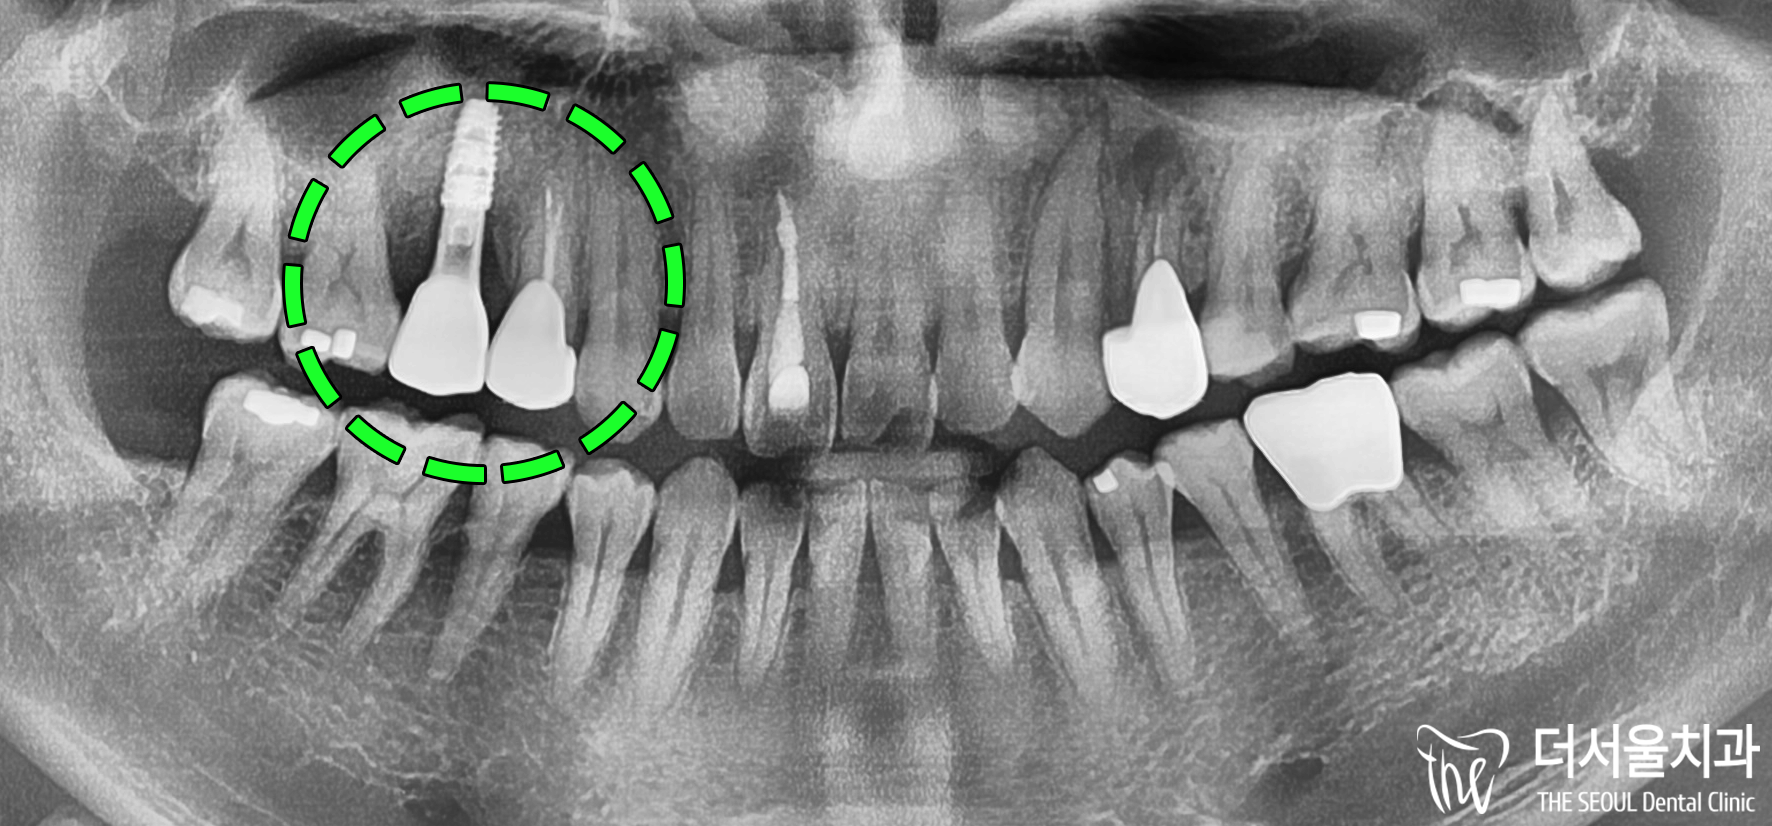

최종 세팅까지 완료된 모습입니다.

주변에 있는 인접치랑 비교했을 때,

티가 나거나 하는 부분없이

깔끔하며 자연스럽게 잘 되었죠?

최종적으로 엑스레이와 CT 촬영을 통해

마무리가 잘 되었는지 확인합니다.

뼈재료는 뼈로 잘 치환되었으며

튼튼하게 자리를 잘 잡았네요.

임플란트 역시 마찬가지로

흔들림없이 고정력을 딱 갖췄구요. 🙂